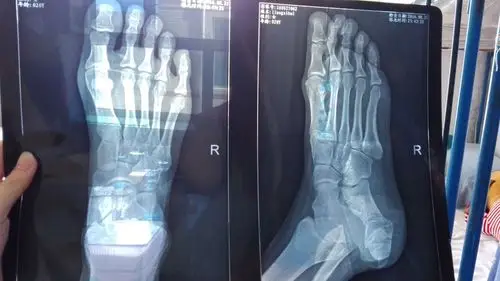

昨晚不小心从楼梯滑倒了,右脚扭伤了,照过x光,疼痛位置一个在脚拇